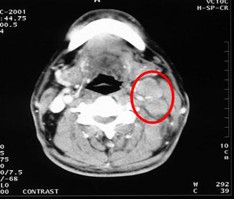

病例1 男,60歲,鼻咽癌Ⅲ 期,T2N2M0,治療前腫瘤充滿鼻咽腔和后鼻腔后緣,23.5cm2。治療方案:今又生瘤內(nèi)注射,1×1012VP/次/周,共6周,并聯(lián)合放療40Gy。治療后:腫瘤完全消退。治療前治療后 病例2 患者病情:…今又生治療病例---食管癌